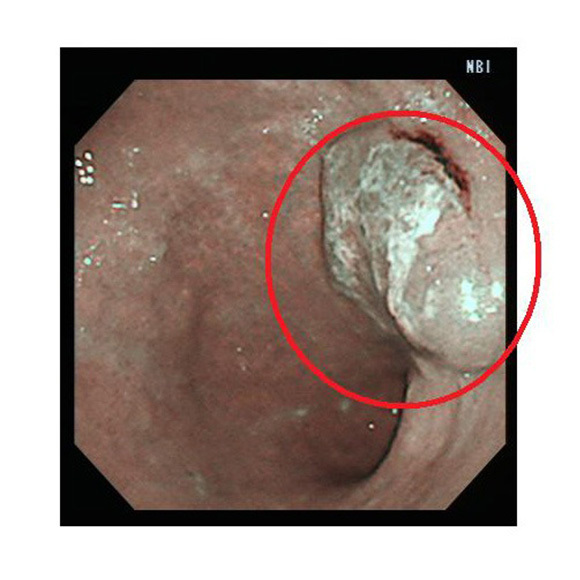

NBI:狭帯域光法システムで光を照らして観察します

NBI

食道・胃・大腸内の様子を明確に画像表示し、より癌を見つけやすくなりました。